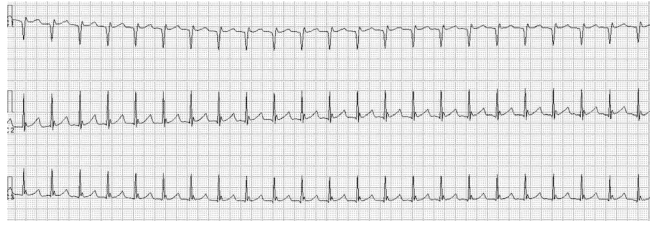

Leia o enunciado a seguir e responda a questão.

Mulher, 68 anos, sem antecedentes mórbidos, apresenta dor torácica ventilatório-dependente, de forte intensidade com piora à inspiração profunda e dispneia intensa. Recebeu alta há 15 dias após internação para cirurgia de correção de fratura de colo de fêmur. Exame físico: bom estado geral, taquipneica leve, afebril, PA = 120x70 mmHg, saturação periférica de oxigênio = 89% em ar ambiente, ausculta cardíaca normal e ausculta pulmonar com estertores crepitantes finos em bases. Realizados eletrocardiograma e tomografia computadorizada de tórax com contraste, ilustrados a seguir.

Provas

Leia o enunciado a seguir e responda a questão.

Mulher, 68 anos, sem antecedentes mórbidos, apresenta dor torácica ventilatório-dependente, de forte intensidade com piora à inspiração profunda e dispneia intensa. Recebeu alta há 15 dias após internação para cirurgia de correção de fratura de colo de fêmur. Exame físico: bom estado geral, taquipneica leve, afebril, PA = 120x70 mmHg, saturação periférica de oxigênio = 89% em ar ambiente, ausculta cardíaca normal e ausculta pulmonar com estertores crepitantes finos em bases. Realizados eletrocardiograma e tomografia computadorizada de tórax com contraste, ilustrados a seguir.

Após internação e monitorização, houve rebaixamento súbito do nível de consciência. A paciente ficou desacordada, sem responder a estímulos verbais ou dolorosos e sem apresentar pulsos centrais e movimentos respiratórios. Uma tira de ritmo cardíaco obtida nesse momento está ilustrada a seguir.

Assinale a alternativa que contém a primeira conduta a ser adotada imediatamente.

Leia o enunciado a seguir e responda a questão.

Mulher, 68 anos, sem antecedentes mórbidos, apresenta dor torácica ventilatório-dependente, de forte intensidade com piora à inspiração profunda e dispneia intensa. Recebeu alta há 15 dias após internação para cirurgia de correção de fratura de colo de fêmur. Exame físico: bom estado geral, taquipneica leve, afebril, PA = 120x70 mmHg, saturação periférica de oxigênio = 89% em ar ambiente, ausculta cardíaca normal e ausculta pulmonar com estertores crepitantes finos em bases. Realizados eletrocardiograma e tomografia computadorizada de tórax com contraste, ilustrados a seguir.

Provas